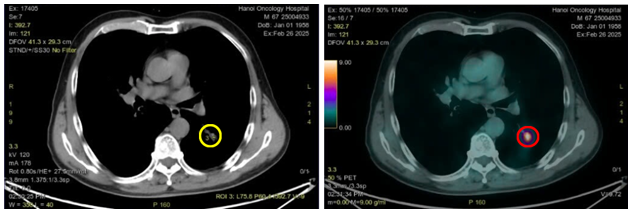

Hình 1: Hình ảnh nốt đặc thùy dưới phổi trái kích thước 10x14mm trên của sổ nhu mô (vòng tròn màu vàng) và cửa sổ trung thất (vòng tròn màu đỏ)

Hình 2: Hình ảnh hạch trung thất ở cửa sổ chủ phổi (vòng trong màu đỏ), kích thước 8x11mm, mất cấu trúc rốn hạch